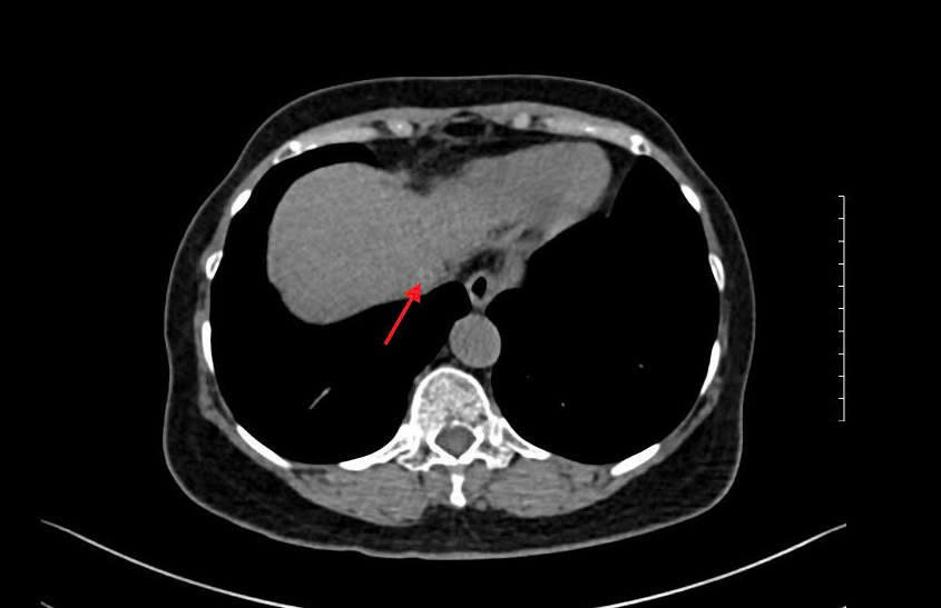

Dr. Le Thanh Quynh Ngan, Head of the Gastroenterology Department, explained that a higher AFP level suggests a greater likelihood of liver cancer. To confirm the diagnosis, a CT scan was ordered, revealing a 0.5 cm tumor. The LI-RADS (Liver Imaging Reporting and Data System) score of 5 confirmed hepatocellular carcinoma. Chronic hepatitis C carries a high risk of progressing to cirrhosis and liver cancer. "Mrs. Binh's case is a typical example of undetected and untreated hepatitis C leading to cirrhosis and liver cancer," Dr. Ngan stated.

MRI results showing Mrs. Binh's liver tumor. Photo: Tam Anh General Hospital